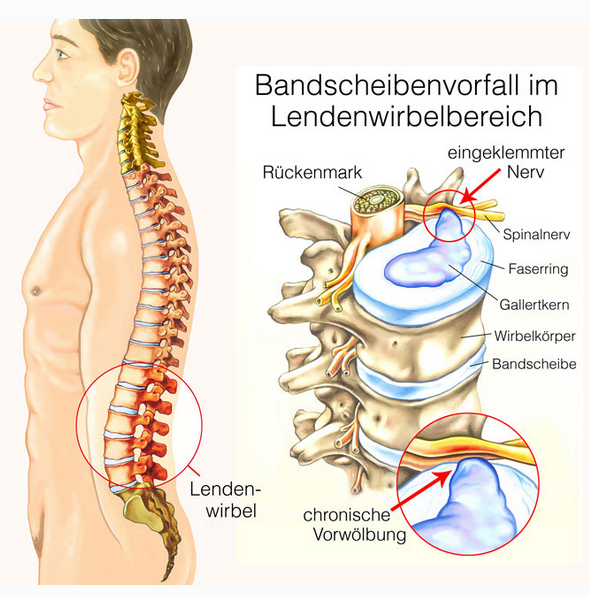

Bandscheiben sind die Druckpolster zwischen den Wirbelkörpern und ermöglichen — ähnlich wie bei einer Fahrradkette — eine Bewegung der sonst knöchernen Wirbelsäule vorwärts, rückwärts und seitwärts sowie eine Rotation. Bandscheiben haben keine Blutgefäße und ernähren sich durch Diffusion mit Nährstoffen aus der umgebenden Flüssigkeit. Ermöglicht wird das durch Druck und Sog. Wenn nun durch die Verspannung der Muskulatur ein Dauerdruck auf den Bandscheiben lastet kommt es zu Ernährungsstörungen — insbesondere des Faserringes, der den gallertartigen Kern ummantelt. Der Faserring reißt langsam ein, der gallertartige Kern wölbt sich an dieser Stelle vor und man spricht von einer/-m Bandscheibenprotrusion/-prolaps. Reißt er komplett durch kommt es zu einem Massenvorfall, der immer eine Akutintervention erfordert, da er auf das Rückenmark drückt. Bei Vorwölbung im Bereich des seitlichen Wirbelloches, wo der Rückenmarksnerv austritt kann es zu einer Kompression kommen. Bedingt durch die Lage der einzelnen Nervenfasern kommt es zunächst zu Schmerz, danach zu Gefühlsstörungen im Bereich des versorgten Gebietes (Dermatom) und letztendlich dann auch zu Muskellähmung, die immer eine sofortige chirurgische Intervention erforderlich machen.